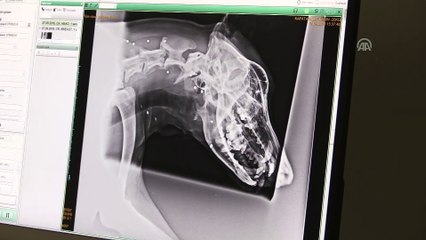

Düzce'nin Kaynaşlı ilçesinde av tüfeğiyle vurulan köpek tedavi altına alındı. brbr İlçeye bağlı Darıyeri Hasanbey köyünde yaşayan B.S., kümesine girdiğini iddia ettiği komşusunun köpeğine ruhsatsız av tüfeğiyle ateş ederek yaraladı.brKöy sakinlerinin ihbarı üzerine İlçe Jandarma Komutanlığı Çevre, Doğa ve Hayvanları Koruma Şube Müdürlüğüne bağlı HAYDİ ekipleri ile "Bipativer" Düzce Hayvanları Koruma Derneği üyeleri olay yerine geldi.br Jandarma ekipleri olayla ilgili soruşturma başlatırken, dernek üyeleri ise yaralı köpeği alarak tedavi edilmesi için veteriner kliniğine götürdü. Ameliyat edilen köpek koruma altına alındı.br B.S. ise jandarma karakolundaki ifadesinin ardından serbest bırakıldı.